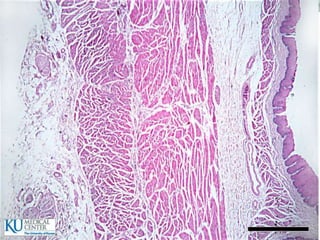

Esófago

 25cm de longitud

 Hacia arriba se continúa con la faringe y hacia abajo

con el estómago

 EPITELIO: Plano estrtificado no queratinizado, en la

parte inferior presenta una transición repentina a

epitelio cilíndrico

 SUBMUCOSA: Fibras colágenas elásticas

 MUSCULAR:

 ADVENTICIA: